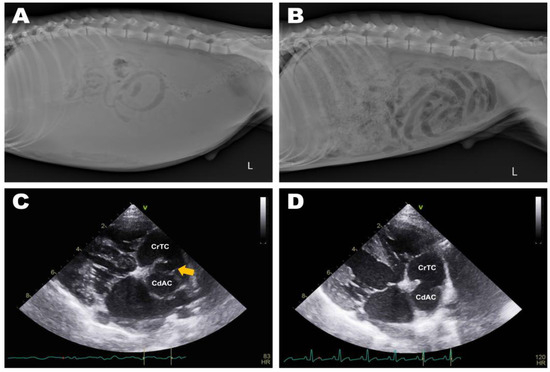

Abdominal radiographs showed severe abdominal distention and a loss of serosal detail (Figure 1); no significant findings were observed apart from these. Transthoracic echocardiography showed an echo-dense, band-like structure within the right atrial chamber, extending from the atrioventricular junction to the free atrial wall (Figure 2A). The right atrium was divided into cranial and caudal chambers. Color Doppler imaging revealed continuous venous blood inflow from the caudal chamber to the cranial chamber through a perforation in the remnant membrane, confirming an abnormal venous blood inflow in the right atrium. An agitated saline study was performed using 3 mL of normal saline to further characterize the flow in the right atrium. Microbubbles were made with saline solution, two syringes, and a three-way stopcock. These were injected in the left cephalic vein and the contrast was noted only in the right atrial cranial chamber and the right ventricle immediately afterward (Figure 2B). When the microbubbles were injected in the left lateral saphenous vein, these reached immediately the right atrial caudal chamber; and some moved into the cranial chamber through a perforated membrane (Figure 2C). This confirmed the presence of a cranial true chamber (CrTC) and cranial vena cava (CrVC) as well as a caudal accessory chamber (CdAC) and caudal vena cava (CdVC). A thoracic computed tomography scan was performed using 30 mL of iohexol contrast agent (Omnipaque, GE Healthcare China). Strong contrast enhancement was observed in the cranial chamber that communicated with the CrVC (Figure 3) during the dextrophase (25 s after contrast injection); in contrast, weak contrast enhancement was observed in the caudal chamber connected to the CdVC. A venous blood inflow obstruction was observed in the right atrium connected to the CdVC, suspected of causing severe ascites. Based on these imaging findings, the patient was diagnosed with CTD, and surgical correction was advised. Both interventional procedures and open-heart surgery can be options for treating CTD. However, considering the potential risk of re-stenosis following interventional treatment, a curative resection involving surgical membranectomy via VIO was planned.

Figure 1. Preoperative abdominal radiography: ventrodorsal (A) and lateral (B) views. Severe abdominal distention and decreased serosal detail were observed due to ascites.